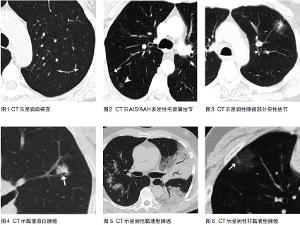

主要與 肺其他 類型的腫瘤相鑑別,其次應與胸膜間皮瘤鑑別,主要依賴病理檢查鑑別,如獲得活組織病理困難,則依靠生物學行為及影像 學表現 相鑑別,但往往鑑別困難。

1. 良性腫瘤:常見的有肺錯構瘤、支氣管肺囊腫、巨大淋巴結增生、炎性肌母細胞瘤、硬化性血管瘤、結核瘤、動靜脈瘺和肺隔離症等。這些良性病變在影像檢查上各有其特點,若與惡性腫瘤不易區別時,應當考慮手術切除。

2. 結核性病變:是肺部疾病中較常見也是最容易與肺癌相混淆的病變。臨床上容易誤診誤治或延誤治療。對於臨床上難於鑑別的病變,應當反覆做痰細胞學檢查、纖維支氣管鏡檢查及其他輔助檢查,直至開胸探查。在明確病理或細胞學診斷前禁忌行放射治療(以下簡稱放療)或化學藥物治療(以下簡稱化療),但可進行診斷性抗結核治療及密切隨訪。結核菌素試驗陽性不能作為排除肺癌的指標。

3. 肺炎:大約有 1/4 的肺癌早期以肺炎的形式出現。對起病緩慢,症狀輕微,抗炎治療效果不佳或反覆發生在同一部位的肺炎應當高度警惕有肺癌可能。

4. 其他:包括發生在肺部的一些少見、罕見的良、惡性腫瘤,如肺纖維瘤、肺脂肪瘤等,術前往往難以鑑別。